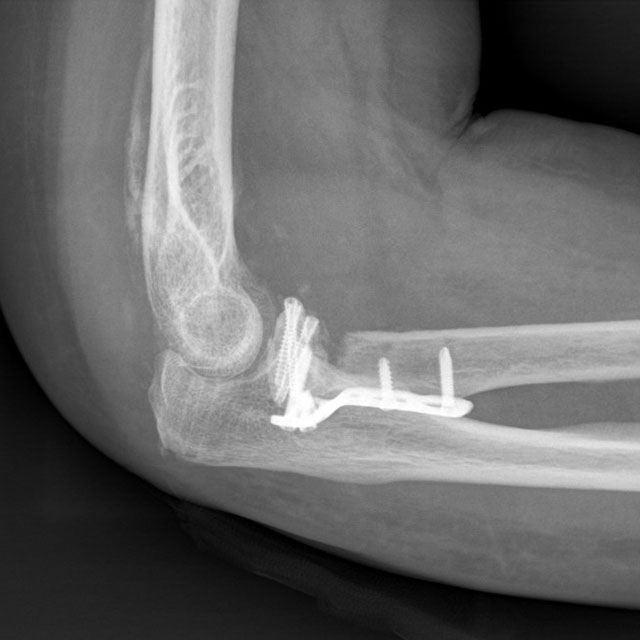

术后复查X片

最终,冯嬢嬢接受了精确的骨折复位和内固定手术。手术团队不仅重视骨折的固定,还对受损的软组织进行了细致的修复,以确保关节的稳定性和功能的完整性。